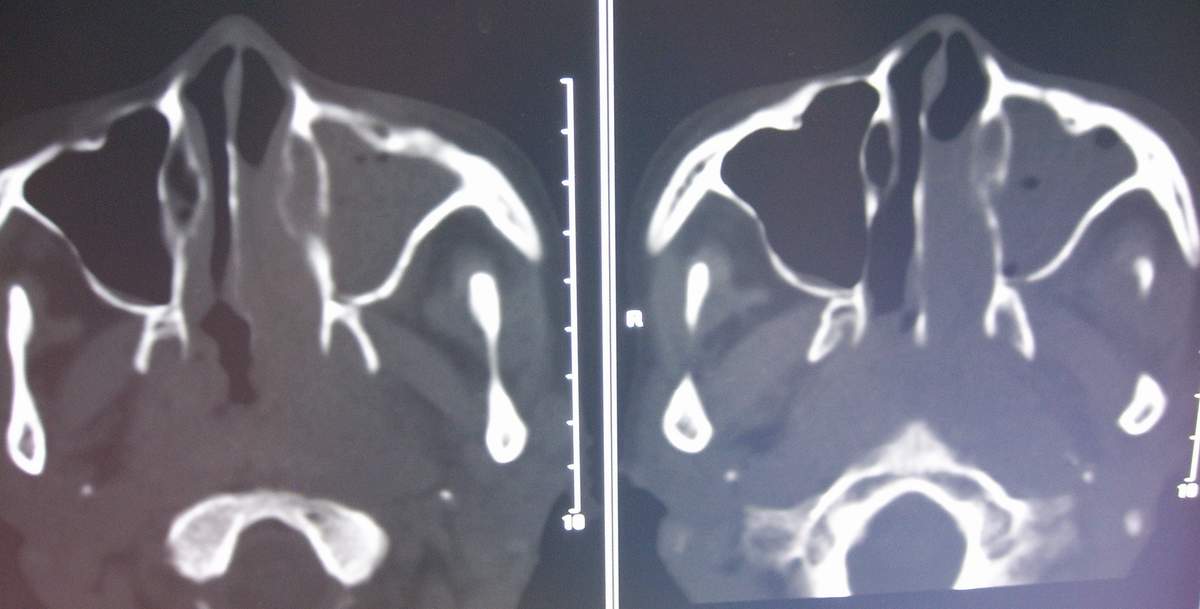

标题: CT7384:[讨论][分享]鼻咽纤维血管瘤? [打印本页]

女,57岁,病史不详。

左侧鼻腔息肉样病变,建议活检或增强扫描。左上颌窦炎。

建议增强,需除外鼻腔及鼻孔息肉伴左侧上颌窦阻塞性炎症.

图像有点少,又没有强化,不太好说。不过鼻咽部纤维血管瘤好发于年青男性

这么大年龄,首先应考虑鼻咽癌伴阻塞性鼻窦炎。

鼻咽纤维血管瘤好发于青少年,有反复鼻腔出血病史,明显强化,此病例年龄偏大,考虑鼻咽癌伴阻塞性鼻窦炎